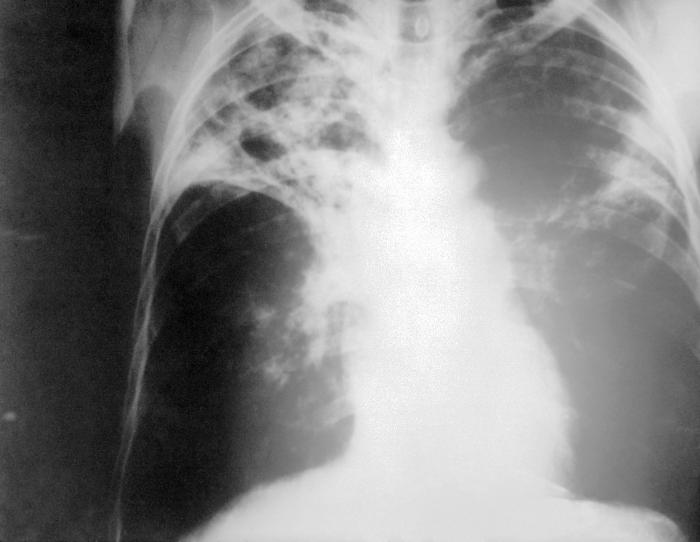

1. Lower Respiratory Infections

At least more than 4 million people are killed each year by lower respiratory infections such as pneumonia and other diseases of the bronchial tubes, windpipe or lungs, including Legionnaire’s disease. This infection spreads through laughing, exhaling, coughing or sneezing.